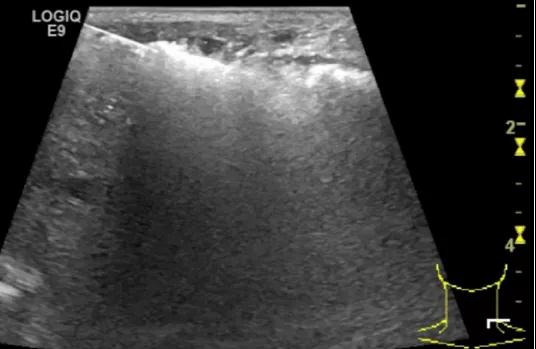

第二例是食管癌患者,术后半年余锁骨上固定淋巴结可触及肿大,疼痛非常明显,系统治疗后无缓解,患者希望通过局部处理缓解症状。造影显示强化信号明显,结节部分区域坏死,故主要针对强化区域从后向前的逐层的消融,皮下进行液体隔离减少烫伤。热消融后影像显示血流增强消失,弹性、硬度增高,一个月后复查显示充盈缺损,完全消融,疗效远超预期。

(病例2图例)